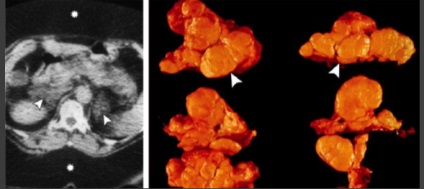

Feocromocitom.

2-8 cazuri la 1 milion. Omul.

F.- este paraganglioma.

F. secreta catecolamină metaboliti + = diagnostic.

Cele mai multe 3-5cm, rotunjite, 35,9 HU ± 9,8 (CT nativ), 10% au calcificări pot fi fibroza, chist, includerea de grăsime, homo- il eterogenă.

De multe ori hipervasculare, dar nu există criterii clare. hiperintensă RMN pe T2VI. Partea f. fără clinica exprimată - accidentală găsi astfel mai mult.

O parte f. cauze ereditare (25-30% din toate f.).

PET / CT 78% sensibilitate (f. Nu mts),

și f. mts cu sensibilitate ≈100%.

De asemenea, PET / CT detectează. pentru adenoamelor și carcinoamelor.

Distinge f. bine și rău este imposibilă fără invazie a structurilor din jur și mts

(În regional l / y, rinichi, ficat, os).

F. variabilă - „imagine cameleon“. Se recomandă să se includă f. în leziunile DD cu densitate scăzută, washout HF rapidă, leziuni chistice cu componenta dominantă, în funcție de parametrii clinici și de laborator.